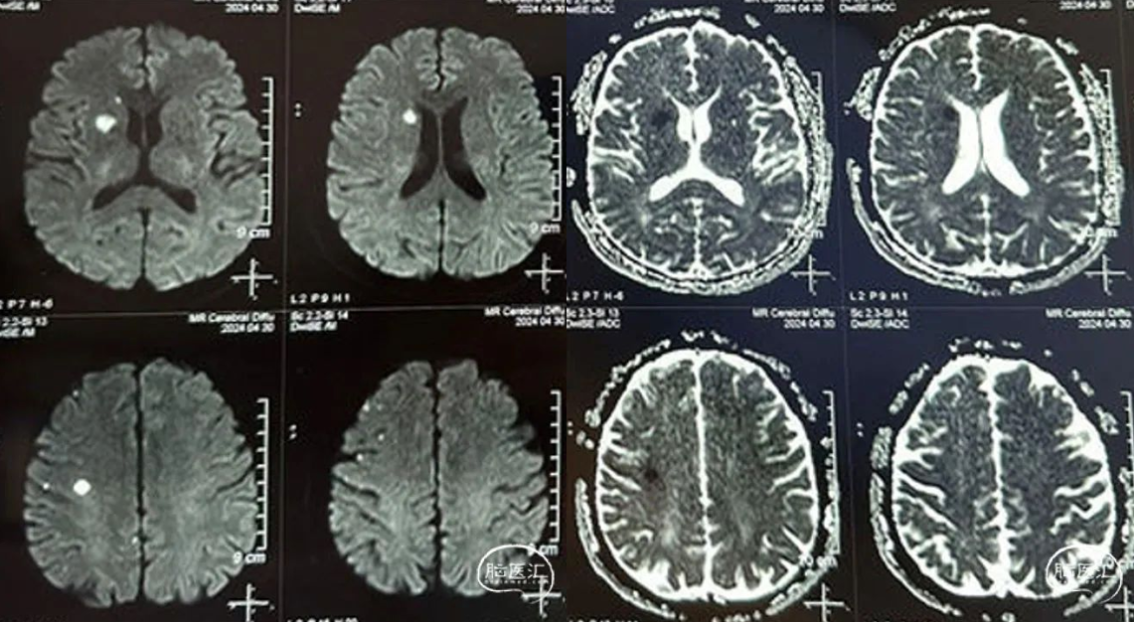

MRI from another hospital showed acute cerebral infarction in the right basal ganglia and frontal lobe.

CTA from another hospital indicated Right internal carotid artery occlusion.